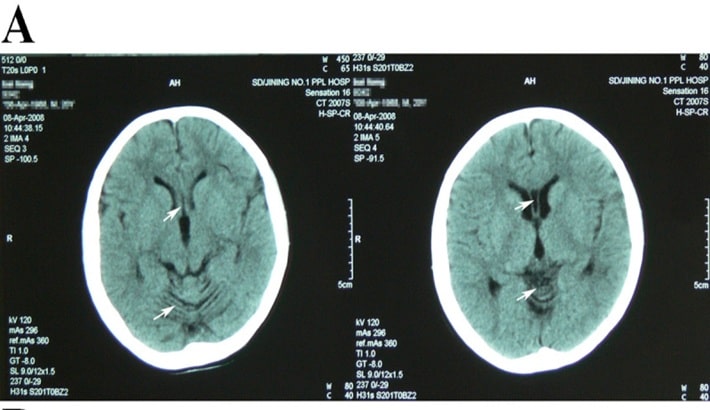

خونریزی مغزی یا هماتوم از خطرناکترین شرایط مغزی است که نیاز به تشخیص فوری و دقیق دارد. در چنین شرایطی، سی تی اسکن مغز بهعنوان سریعترین و قابلاعتمادترین روش تصویربرداری شناخته میشود. این روش میتواند حتی کوچکترین مقدار خونریزی را در عمق بافت مغز یا اطراف آن نشان دهد؛ همچنین پزشک را در انتخاب درمان فوری یاری کند.

نقش سی تی اسکن مغز در تشخیص خونریزی

سی تی اسکن مغز با استفاده از اشعه ایکس و فناوری کامپیوتری، تصاویر دقیق و چندبعدی از بافتهای داخلی مغز تهیه میکند. در این تصاویر، نواحی دچار خونریزی بهصورت روشنتر از بافت طبیعی مغز دیده میشوند. این ویژگی کمک میکند تا نوع و محل خونریزی مغزی بهسرعت مشخص شود.

انواع خونریزیهایی که در سی تی اسکن مغز قابل تشخیصاند:

سی تی اسکن مغز میتواند انواع مختلف هماتوم را از یکدیگر تفکیک کند.

خونریزی زیرعنکبوتیه:

در فضای بین مغز و لایههای اطراف آن اتفاق میافتد و با سی تی اسکن مغز بدون تزریق بهوضوح قابل مشاهده است.

مزیت سی تی اسکن مغز در شرایط اورژانسی

یکی از مزایای بزرگ سی تی اسکن مغز ، سرعت بالا و توانایی تشخیص فوری است. برخلاف امآرآی که زمان بیشتری میبرد، سی تی اسکن میتواند در کمتر از ده دقیقه انجام شود. این ویژگی در بیمارانی که دچار ضربه مغزی، سکته یا کاهش سطح هوشیاری هستند حیاتی است.